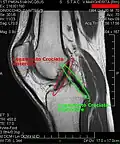

Both anterior cruciate ligament (ACL) and posterior cruciate ligaments (PCL) are hypointense on both T1 and T2 weighted images of MRI. However, some high signal striations are often seen at the distal part of the ACL, making ACL higher intensity than PCL on MRI scans.[20]

-

Knee MRI (PD TSE FS sagittal) -

Knee MRI (T1 TSE sagittal) -

Knee MRI (sagittal TSE FS)